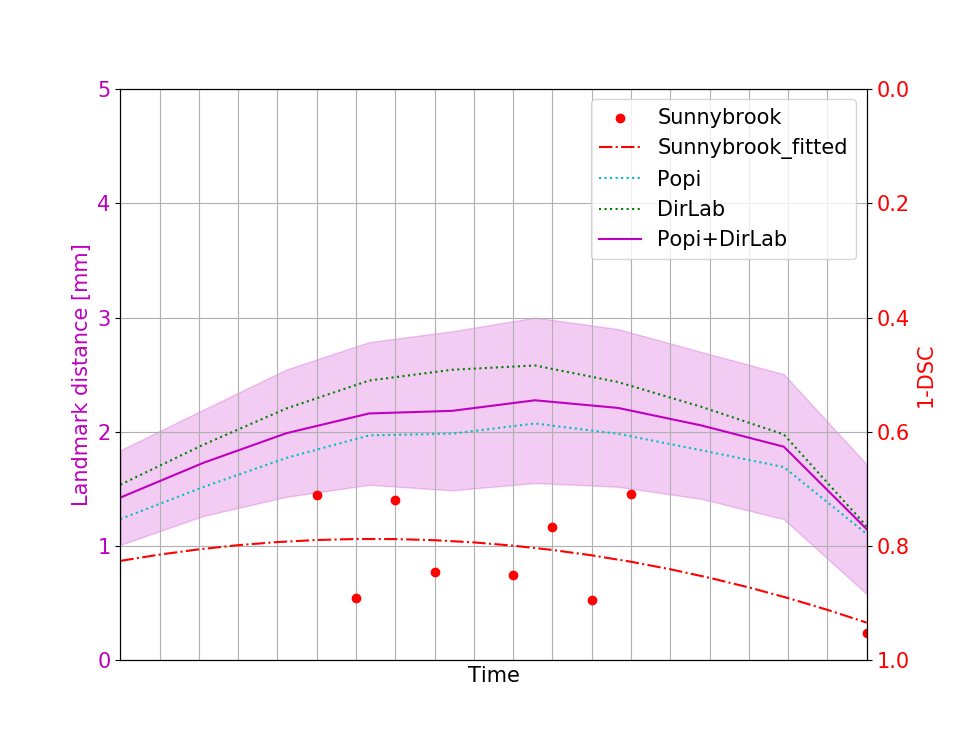

The initial average landmark distance between consecutive phase images was 2.25 1.55 mm for the Popi datasets and 2.19 2.02 mm for the DirLab datasets. The proposed registration algorithm could decrease the average distance to 1.24 0.90 mm and 1.54 1.31 mm, respectively. For a comparison with existing 4D registration methods we applied the publicly available method by [23] to the respiratory datasets and achieved average registration errors similar to the ones of our method: 1.56 1.42 mm for the DirLab and 1.11 0.87 mm for the Popi datasets. The construction of trajectories for voxels requires the combination of all DVF of a 4D dataset. As a consequence the registration error at the start of a trajectory gets propagated over time and increases or decreases with the combination of the different DVF. In Fig. 4 the error evolution is visualised for the three test datasets. At the beginning the mean registration error is 1.54 mm for the DirLab datasets and 1.24 mm for the Popi datasets. The error then increases to a mean of 2.58 mm for DirLab and 2.07 mm for Popi in the middle of the periodic motion. In the end of the breathing cycle the error falls to an error around 1 mm for both datasets. A similar error propagation pattern could be measured for the Sunnybrook datasets. For the Sunnybrook datasets segmentations are only available for the extreme phases, which allows only four comparisons per dataset. When starting with the end-diastolic phase a comparison in the middle of the cyclic motion to the end-systolic segmentation and in the end of the cycle motion to the original end-diastolic segmentation is possible. The same applies when starting with the end-systolic segmentation. In Fig. 4 the red dots indicate the measured DSC overlap, the red dotted line was fitted to the dots and estimates the DSC overlap for phase images without a segmentation available. Compared to a direct registration of the maximum exhale and inhale phases the registration error increased on average by 0.48 mm with the combination of the DVF. The average registration error for the extreme phases in the Popi dataset increased from 1.46 1.59 mm to 1.98 1.56 mm when we registered the whole 4D dataset instead of the two extreme phases solely. The same analysis reported an increase from 1.83 2.35 mm to 2.54 2.01 mm for the DirLab images and and decrease in the DSC from 0.86 0.10 to 0.79 0.14 for the Sunnybrook data. The DVF of the 4D evaluation showed a FoF of 0.02 % and an average Jacobi determinant of 1.00 0.06.

V-D Downsampling And Few Shot Learning

When we used only the first two layers of our network for registration the performance decreased slightly but the gain in computation time was huge. The average registration error for registering 3D respiratory images was 1.84 1.88 mm compared to 1.70 2.15 mm with all 3 layers. The computation time for two 3D images was on average 4 minutes, for 4D datasets the average time needed for registration increased to 8 minutes. The peak in error propagation increased to an average value of 2.32 1.55 mm, 3.08 2.27 mm and 0.75 0.14 DSC for the Popi, DirLab and Sunnybrook datasets, respectively. The few shot analysis on the DirLab dataset worked only for a setting with two downsampling layers. Training the third layer always resulted in an increase of the registration error for the dataset to be registered. Which is an indication that the network could not learn a general representation of detailed deformation from the limited amount of training data. Downsampling layer 1 and 2 were trained for 200 and 250 epochs, respectively. Applying the trained 2 layer models to the test data resulted in an registration error of 4.43 2.94 mm, but by fine tuning the model for 50 epochs the registration error could be decreased to 2.16 2.20 mm, which is comparable to the registration error of the one shot approach with 2.00 2.03 mm for the DirLab dataset and 2 layers. With the few shot approach the computation time could be reduced by a factor of 4 to 1 minute.